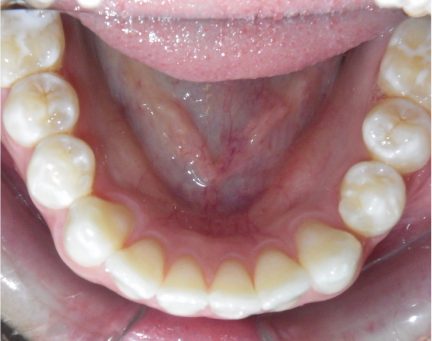

État initial

État final